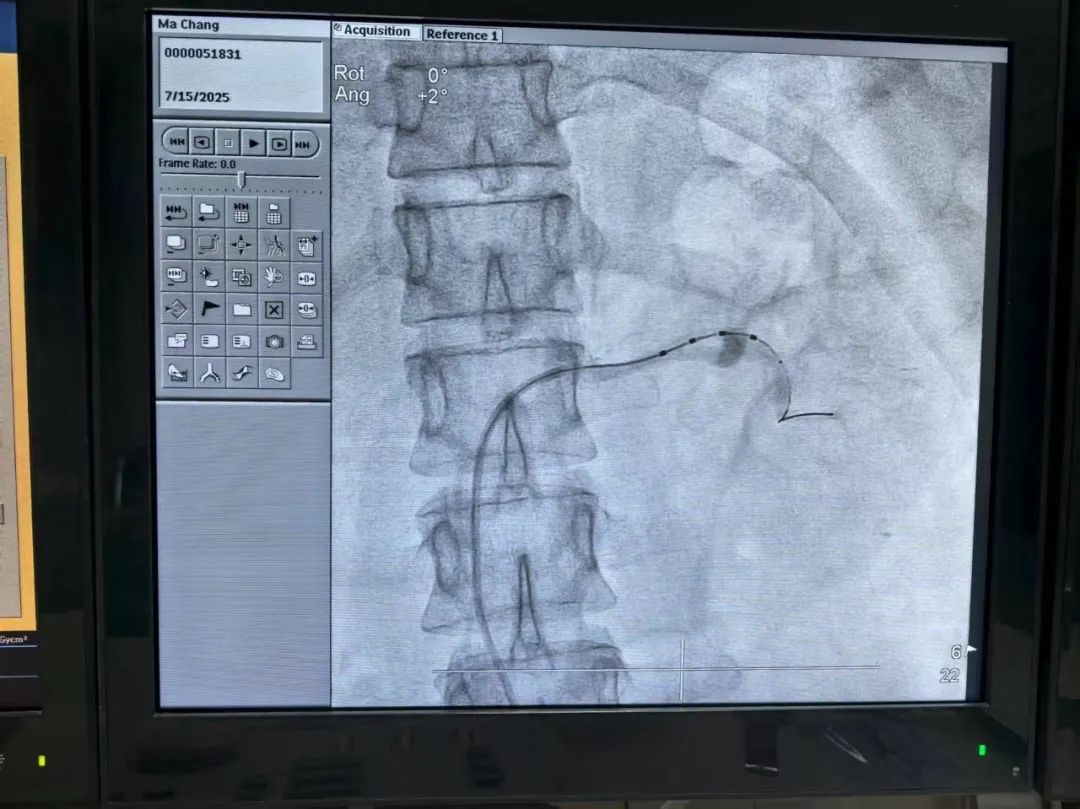

手术过程中,团队通过股动脉穿刺,将多极射频消融导管精准置入双侧肾动脉。术中,麻醉科制定了全麻方案以保障患者安全,导管中心技师、护士团队默契配合,对肾动脉主干及分支的交感神经位点进行消融。

手术历时1小时,左右肾动脉共消融46个位点,术中无不良反应。